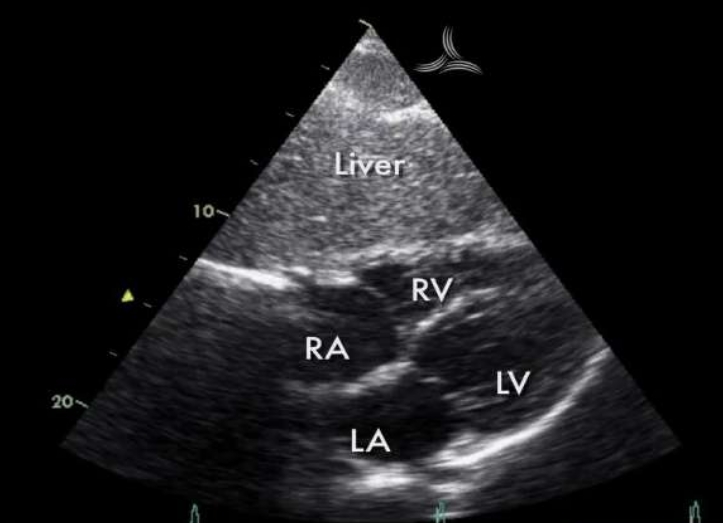

<p>What view is this?</p>

What view is this?

Subcostal

<p>What view would be obtained here?</p>

What view would be obtained here?

Subcostal 4ch View

Subcostal 4ch

Why is subcostal 4ch good?

Best view to access RV free wall, IVS, and IAS

What can be seen in subcostal 4ch

Liver appearance

4 chambers

IAS (perpendicular), IVS

MV, TV